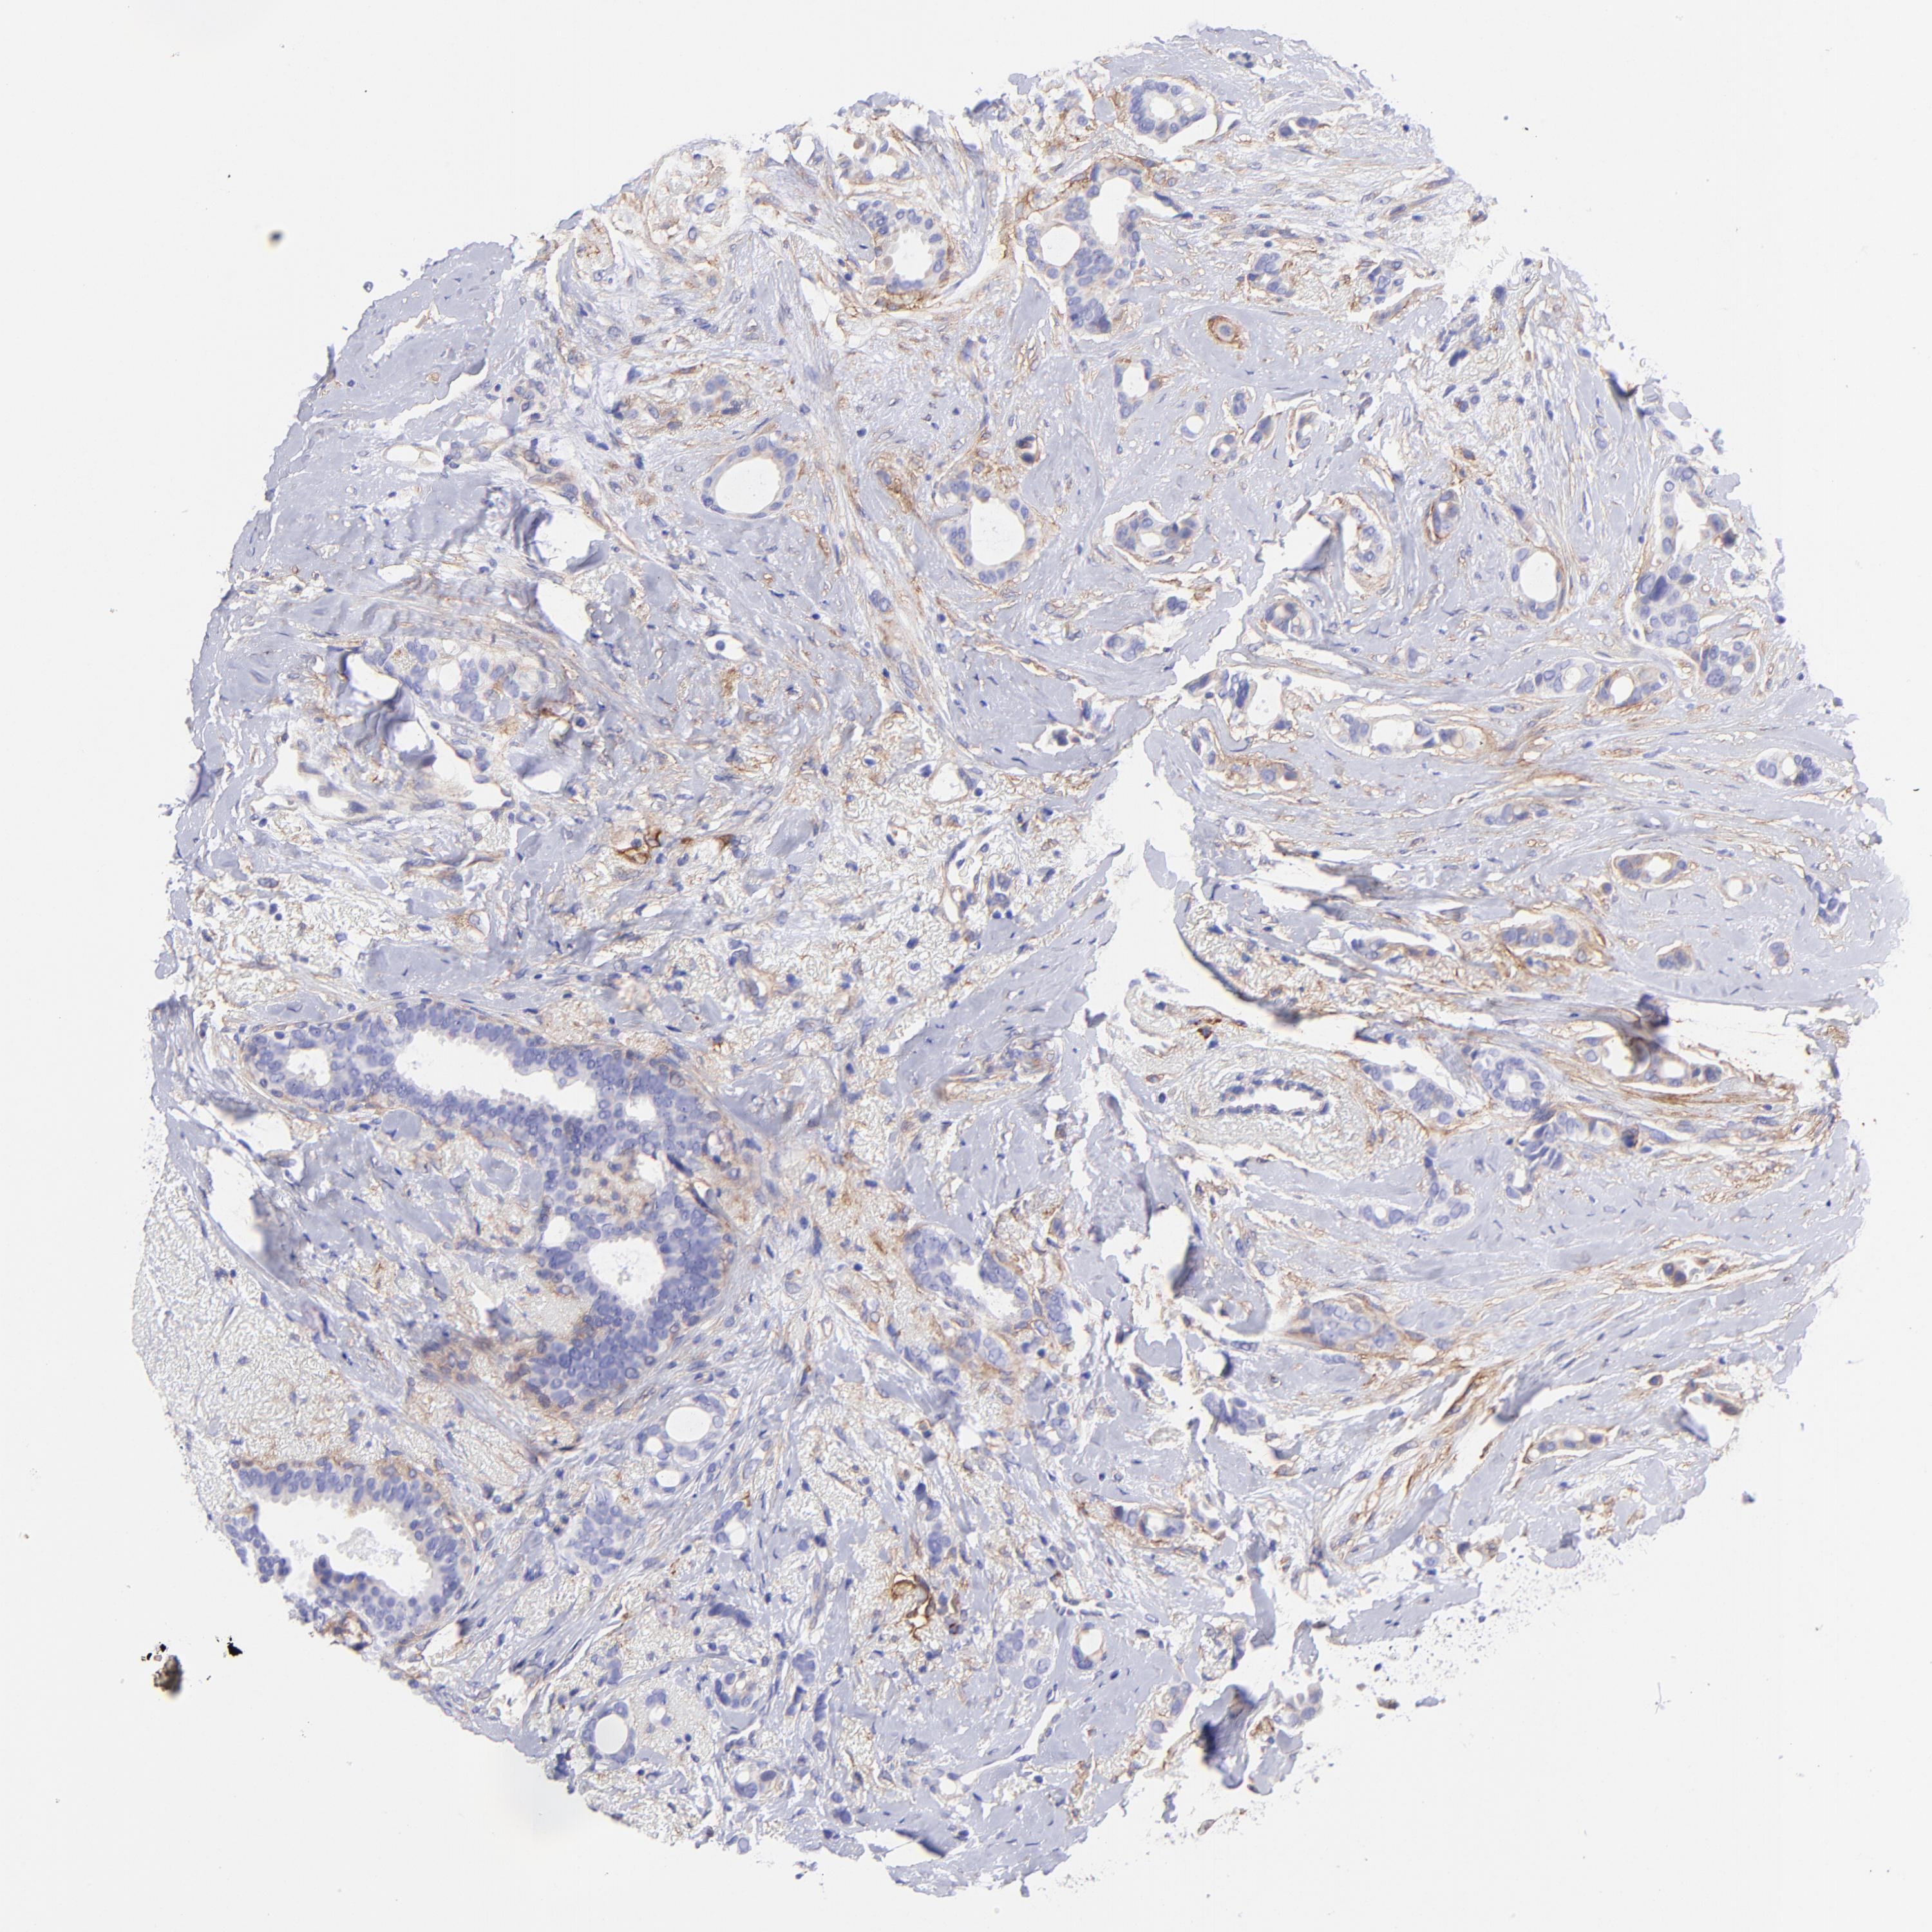

BRCA TCGA BRCA VALIDATION PROTEIN EXPRESSION